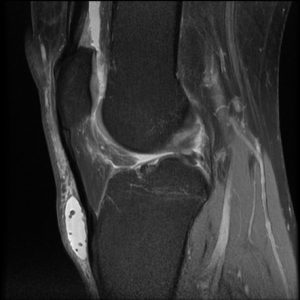

In figure 4 the site of inflammation is lower in the bursa than that seen in figure 2. The fluid is again high signal intensity; however, there are multiple small hypointense bodies within it, likely representing some intrasynovial debris.

Figure 4